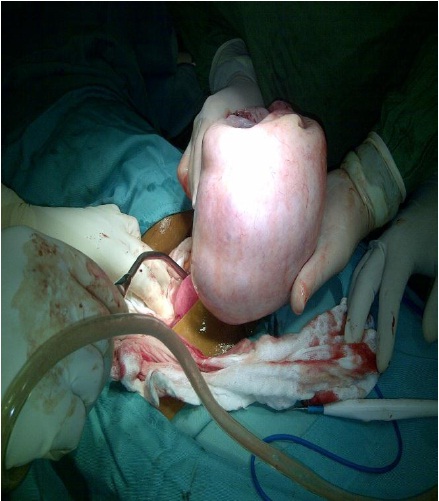

TERATOMA DE OVARIO

Antonio Alvarado Armuelles, Emanuel Tejeira

46-47